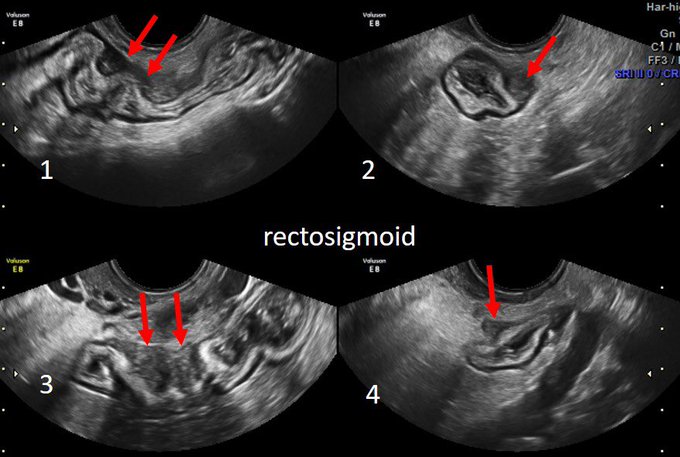

Transvaginal US after bowel prep is the best imaging modality to investigate bowel endometriosis- multiple bowel lesions, 33 yo, infertility for 1 year